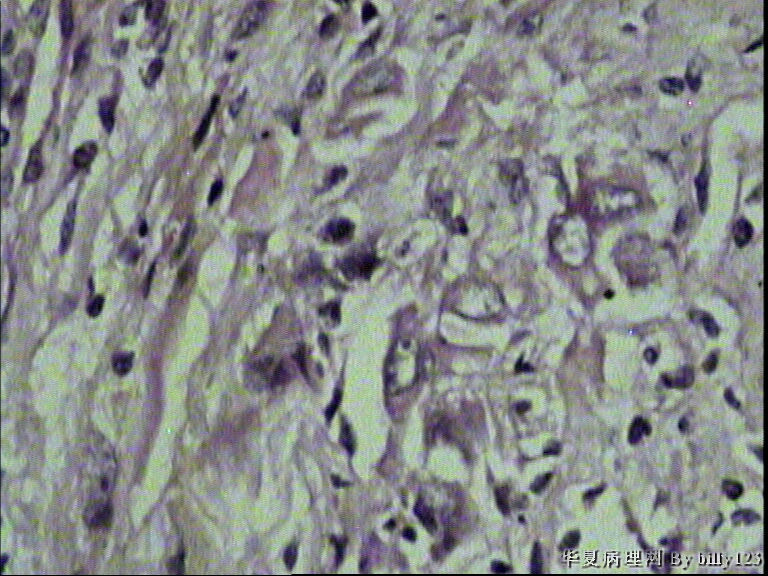

纤支镜活检,女性,75岁,请各位老师指教!

图1